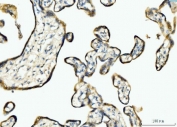

IHC staining of FFPE human placental tissue with BCKDK antibody. HIER: boil tissue sections in pH8 EDTA for 20 min and allow to cool before testing.